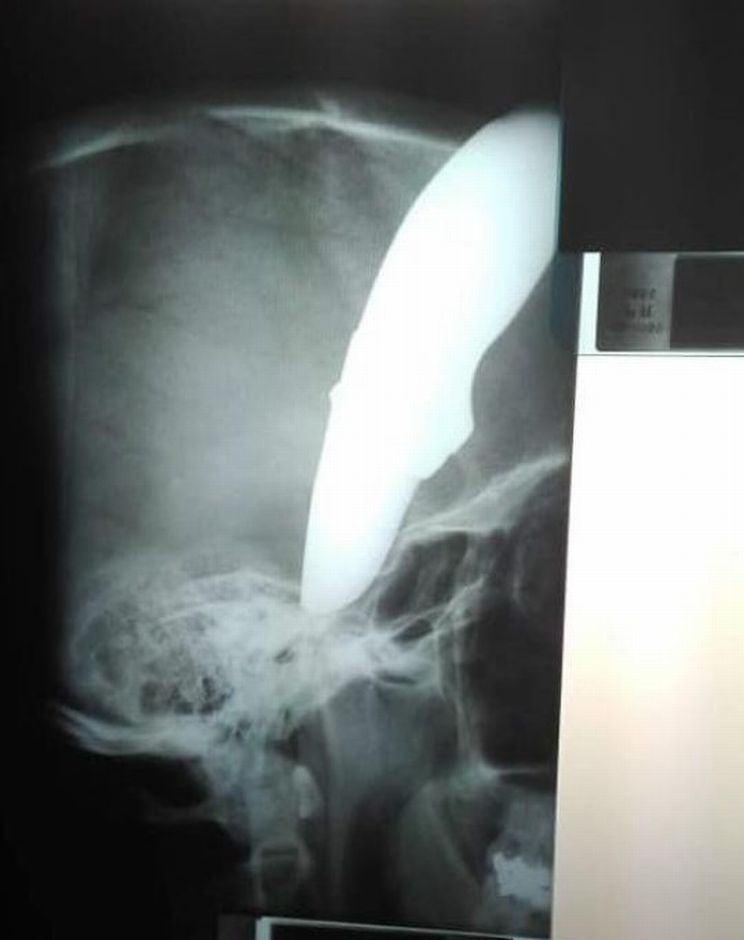

Gambar x-ray tikaman di kepala Shaun. -fotoJamiePyatt

"Pesakit itu sangat bertuah kerana bilah pisau itu bengkok dan tertusuk di bahagian luar tengkoraknya.

"Dia sangat bernasib baik kerana pisau tidak terkena tempat yang boleh membawa maut.